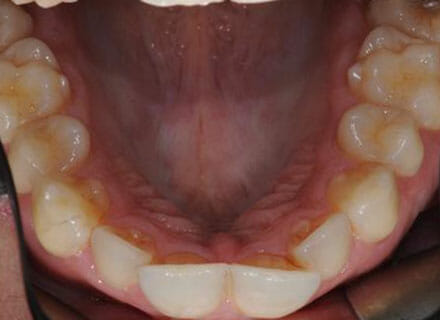

In this case, we needed to reduce the size of the central incisors as they were just too big. This combined with the crowding at the front had caused the lateral incisors to become trapped inside, pushing the big central incisor teeth forwards even more. After reducing the big teeth to a normal size we started with fixed clear bracket brace treatment and were able to complete this case in a little over a year.